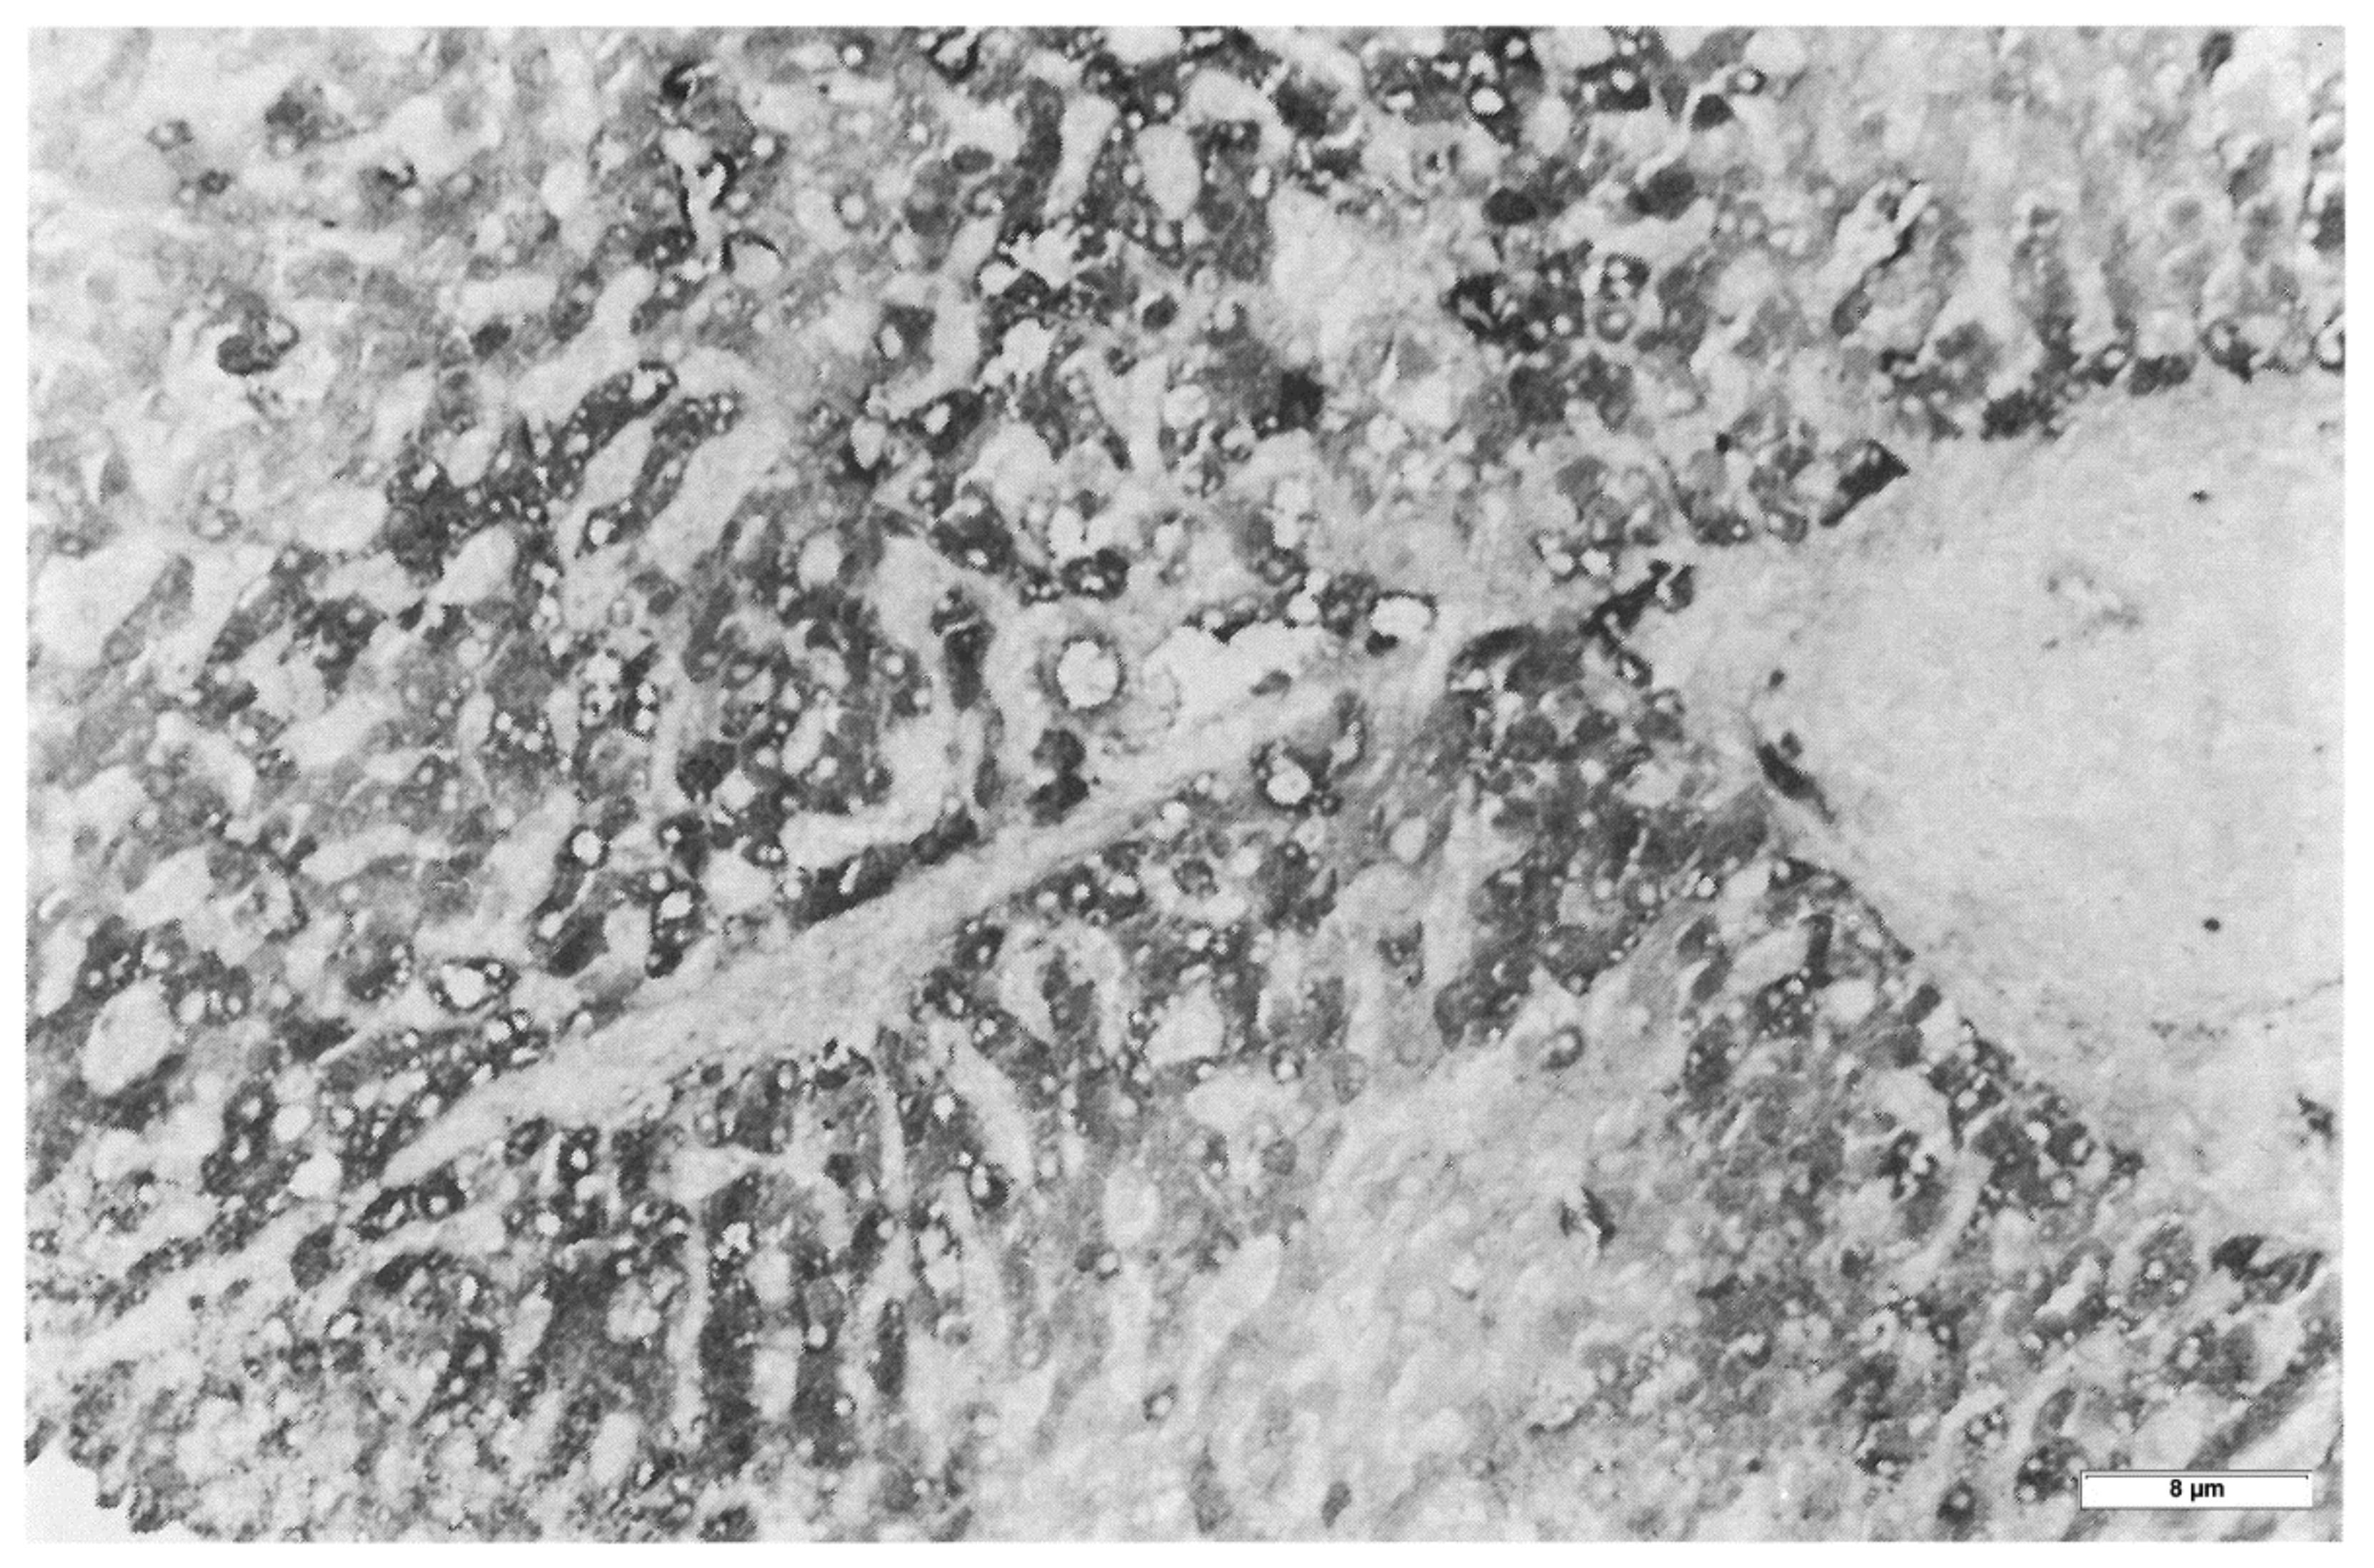

In Pi MZ livers the intralumenal AAT could present a yet undescribed feature made up of fibrils, and tangles of filaments (Figure 9).

Figure 9. Pi MZ patient liver. The electronmicriphotpgraph shows AAT like material in dilated cisternae of the RER. The intraluminal material appears in the form of addensed granules. In a few cisternae the material is loose and made up of fragmented tangle filaments. This feature is more obvious in dilated cisternae nearly empty (single arrowheads and double arrow-head). The hepatocyte contains abundant glycogen (circle), mitochondria (M) and a multivesiculr body (Mb) (EM × 15.725).